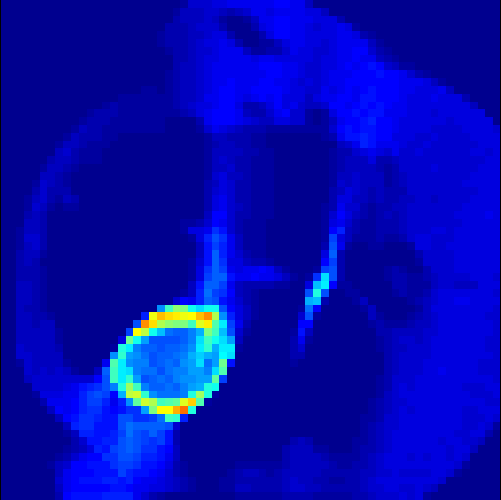

5.2 Monte Carlo Simulation

In order to test the behaviour of the proposed method in a more realistic, random-based test case, we performed a Monte Carlo simulation for dynamic SPECT imaging. First, we created a simple image phantom consisting of an outer and two inner circles which represents the structure of the region of interest (see figure 8(a)). Within those regions we assumed concentration curves over a time period of 90 time steps as displayed in figure 8(b). Based on the tracer intensity in an image frame at each time step, we created a variable number of random decay events (where the number is proportional to the average concentration in one pixel in the whole image frame per time step) with a probability proportional to the concentration in every subregion. They are detected by a virtual double head gamma camera rotating around the patient by 46 degrees per time step, which consists of 374 detector bins. Every simulated decay event is projected onto the scanner and counted by the corresponding detector bin.

In two different tests we fixed the number of events counted by the detector equal to (resp. ) times the average concentration in one pixel. The resulting sinogram images of the accumulated counts in each bin are shown in figure 9.

Based on the sinogram data we applied the proposed algorithm in order to reconstruct the original image sequence. The results for both test cases are shown in figure 10.

As one can see, the method is able to reconstruct the regions properly, even in case of a low count number. Within a number of iterations (average of 100 outer and 10000 inner iterations), the algorithm presents a reasonable reconstruction of the region of interest and the corresponding regional tracer concentration curves. Here, the parameters were not optimized as in the case of the synthesized data sets in the previous section, but kept fixed as , and . With futher optimized parameter values one could possibly provide even better results.